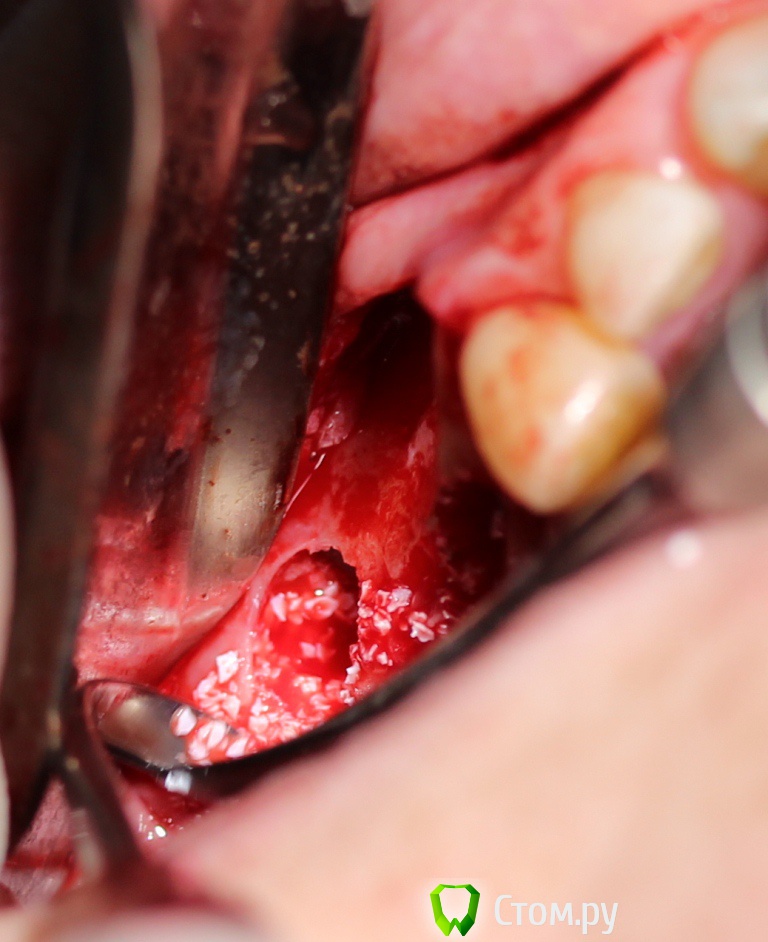

zzkz Опубликовано 18 апреля, 2014 Поделиться Опубликовано 18 апреля, 2014 Спасибо коллегам за вдохновение! Хотя есть не радующие моменты, шел на риск. Фото третьего ассистента немного размыто. Пока не получается отладить(в процессе) Синус+ Небольшое расщепление+ био осс под Ламину.Швы толстые викрил 4-0 - другого не оказалось под рукой, был Пролен 6-0(сомнения что прорежут слизистую) Из вопросов которые возникли 1. винтов не оказалось маленьких(выяснилось во время операции), пришлось фиксировать на винты длиной 10мм в графт в пазухе.что то из за этого может произойти как думаете? 2. импланты с нулевым торком(не надо было делать пропилы), рукой установил, боялся даже заглушку сильно крутить? не чревато ли? 3. Импланты вроде ставил параллельно, а на снимке корявенько, панорамник что ли врет? 1 Ссылка на комментарий